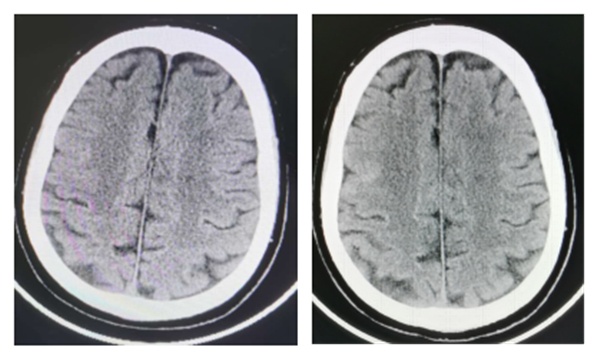

术后CT未见新增梗死病灶(右术前,左术后)